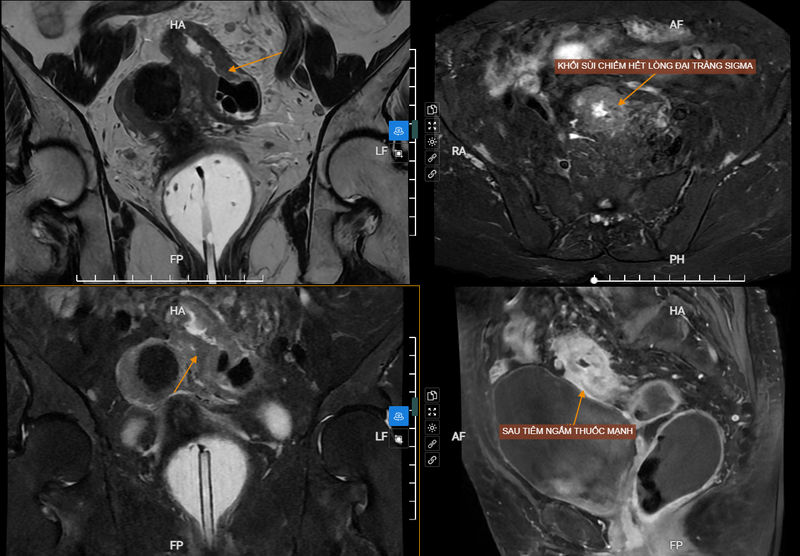

Vị trí đại tràng sigma (xích-ma) nằm gần nhất với trực tràng và hậu môn, là một phần của ruột già. Khi tế bào ung thư tăng sinh đột biến, xâm lấn tới các mô xung quanh niêm mạc đại tràng lâu dần sẽ hình thành ung thư đại tràng sigma. Nếu phát hiện trễ, ung thư đại tràng sigma có khả năng gây tử vong rất cao. Việc nhận biết, phát hiện và thăm khám thường xuyên, kịp thời có ý nghĩa rất quan trọng trong việc phòng ngừa và điều trị căn bệnh này.